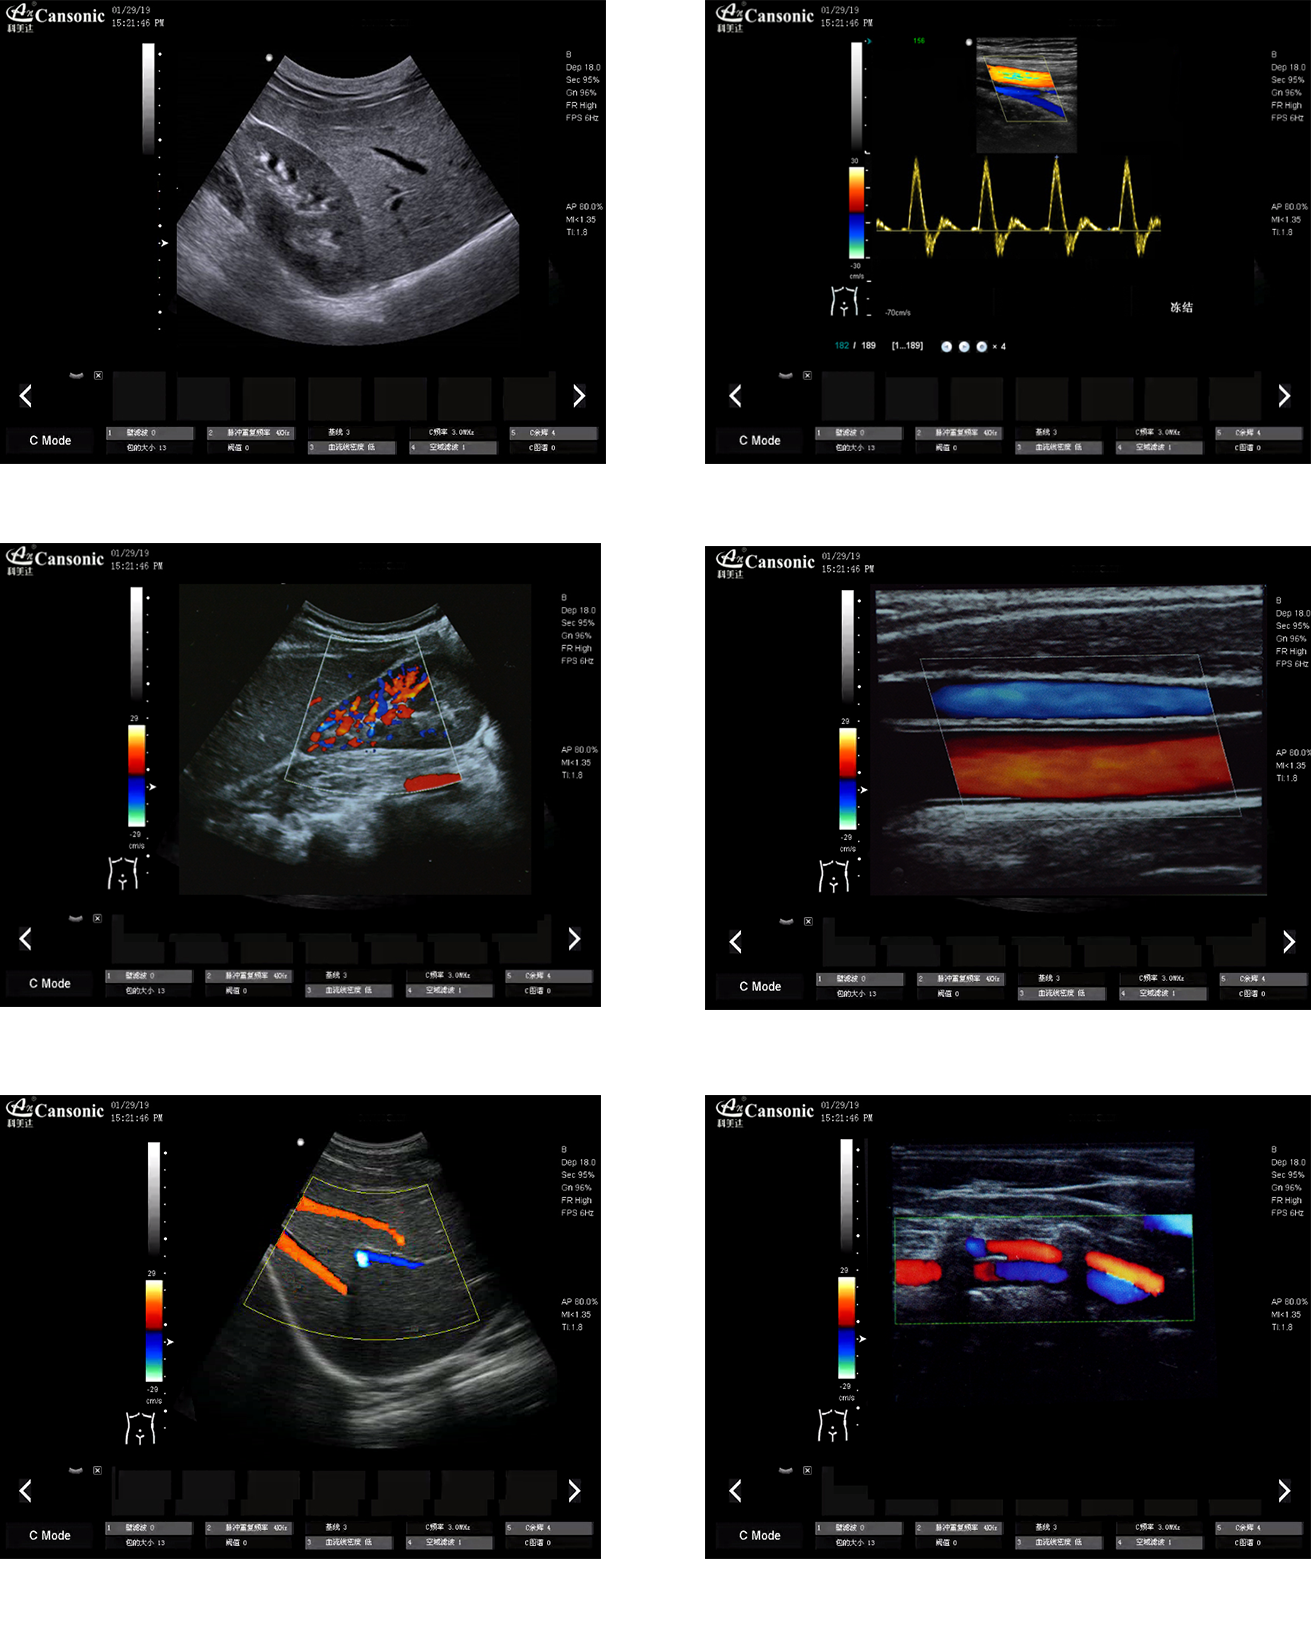

科美達K10圖像實例